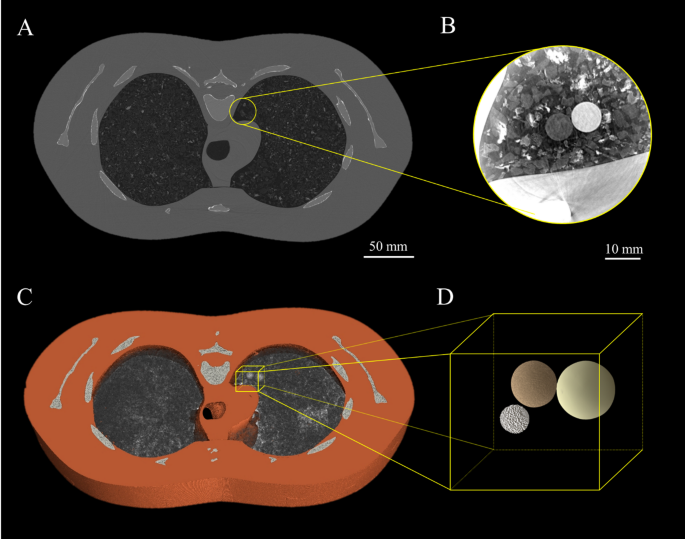

The data gathered in this study included full chest CT data captured with an Eiger detector and ROI CT data captured with a Ruby detector, allowing us to show the position of the region-of-interest relative to the whole lung, provided in Fig. 4. The tumours were placed towards the centre of the lung, a location chosen in order to include air, tissue, bone and neoprene to mimic surrounding lung tissue.

(A) is the chest insert that mimics the pulmonary vasculature. (B) is the foam chest cavity insert that mimics the soft tissue of the lung. (C) is the shredded neoprene which was used for this study, providing a range of length scales and densities not seen in the commercial inserts shown in (A) and (B). (D) shows the placement of the simulated tumours within the chest cavity surrounded by shredded neoprene. The tumours are (a) − 800 HU at 5 mm, (b) − 630 HU at 8 mm, (c) + 100 HU at 10 mm and (d) + 100 HU at 5 mm.

Four of the simulated tumours were placed inside the chest cavity of Lungman for this experiment as seen in Fig. 2D. Three of these spherical tumours of varying density are visible in the CT slices in Figs. 3, 4 and 5. The smallest and lowest density tumour, shown in Figs. 2D, 3 and 4 with visible texture, has a Hounsfield unit value of − 800. The tumour seen in the centre of the images has a Hounsfield unit value of − 630 and the brightest or highest density (most highly attenuating) tumour has a Hounsfield unit value of + 100.